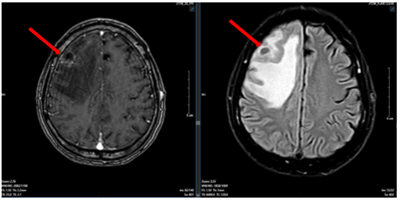

Ca lâm sàng:Hiệu quả điều trị đích bằng Osimertinib ở bệnh nhân UT biểu mô tuyến của phổi giai đoạn IV có đột biến gen EGFR L858R (Exon 21) tại Trung tâm YHHN&UB-Bệnh viện Bạch Mai

Ung thư phổi là một trong những ung thư có tỷ lệ mắc và tử vong cao nhất trên toàn thế giới. Theo GLOBOCAN 2022, ung thư phổi đứng thứ hai về số ca mắc mới với khoảng 2,5 triệu trường hợp mỗi năm và là nguyên nhân hàng đầu gây tử vong do...